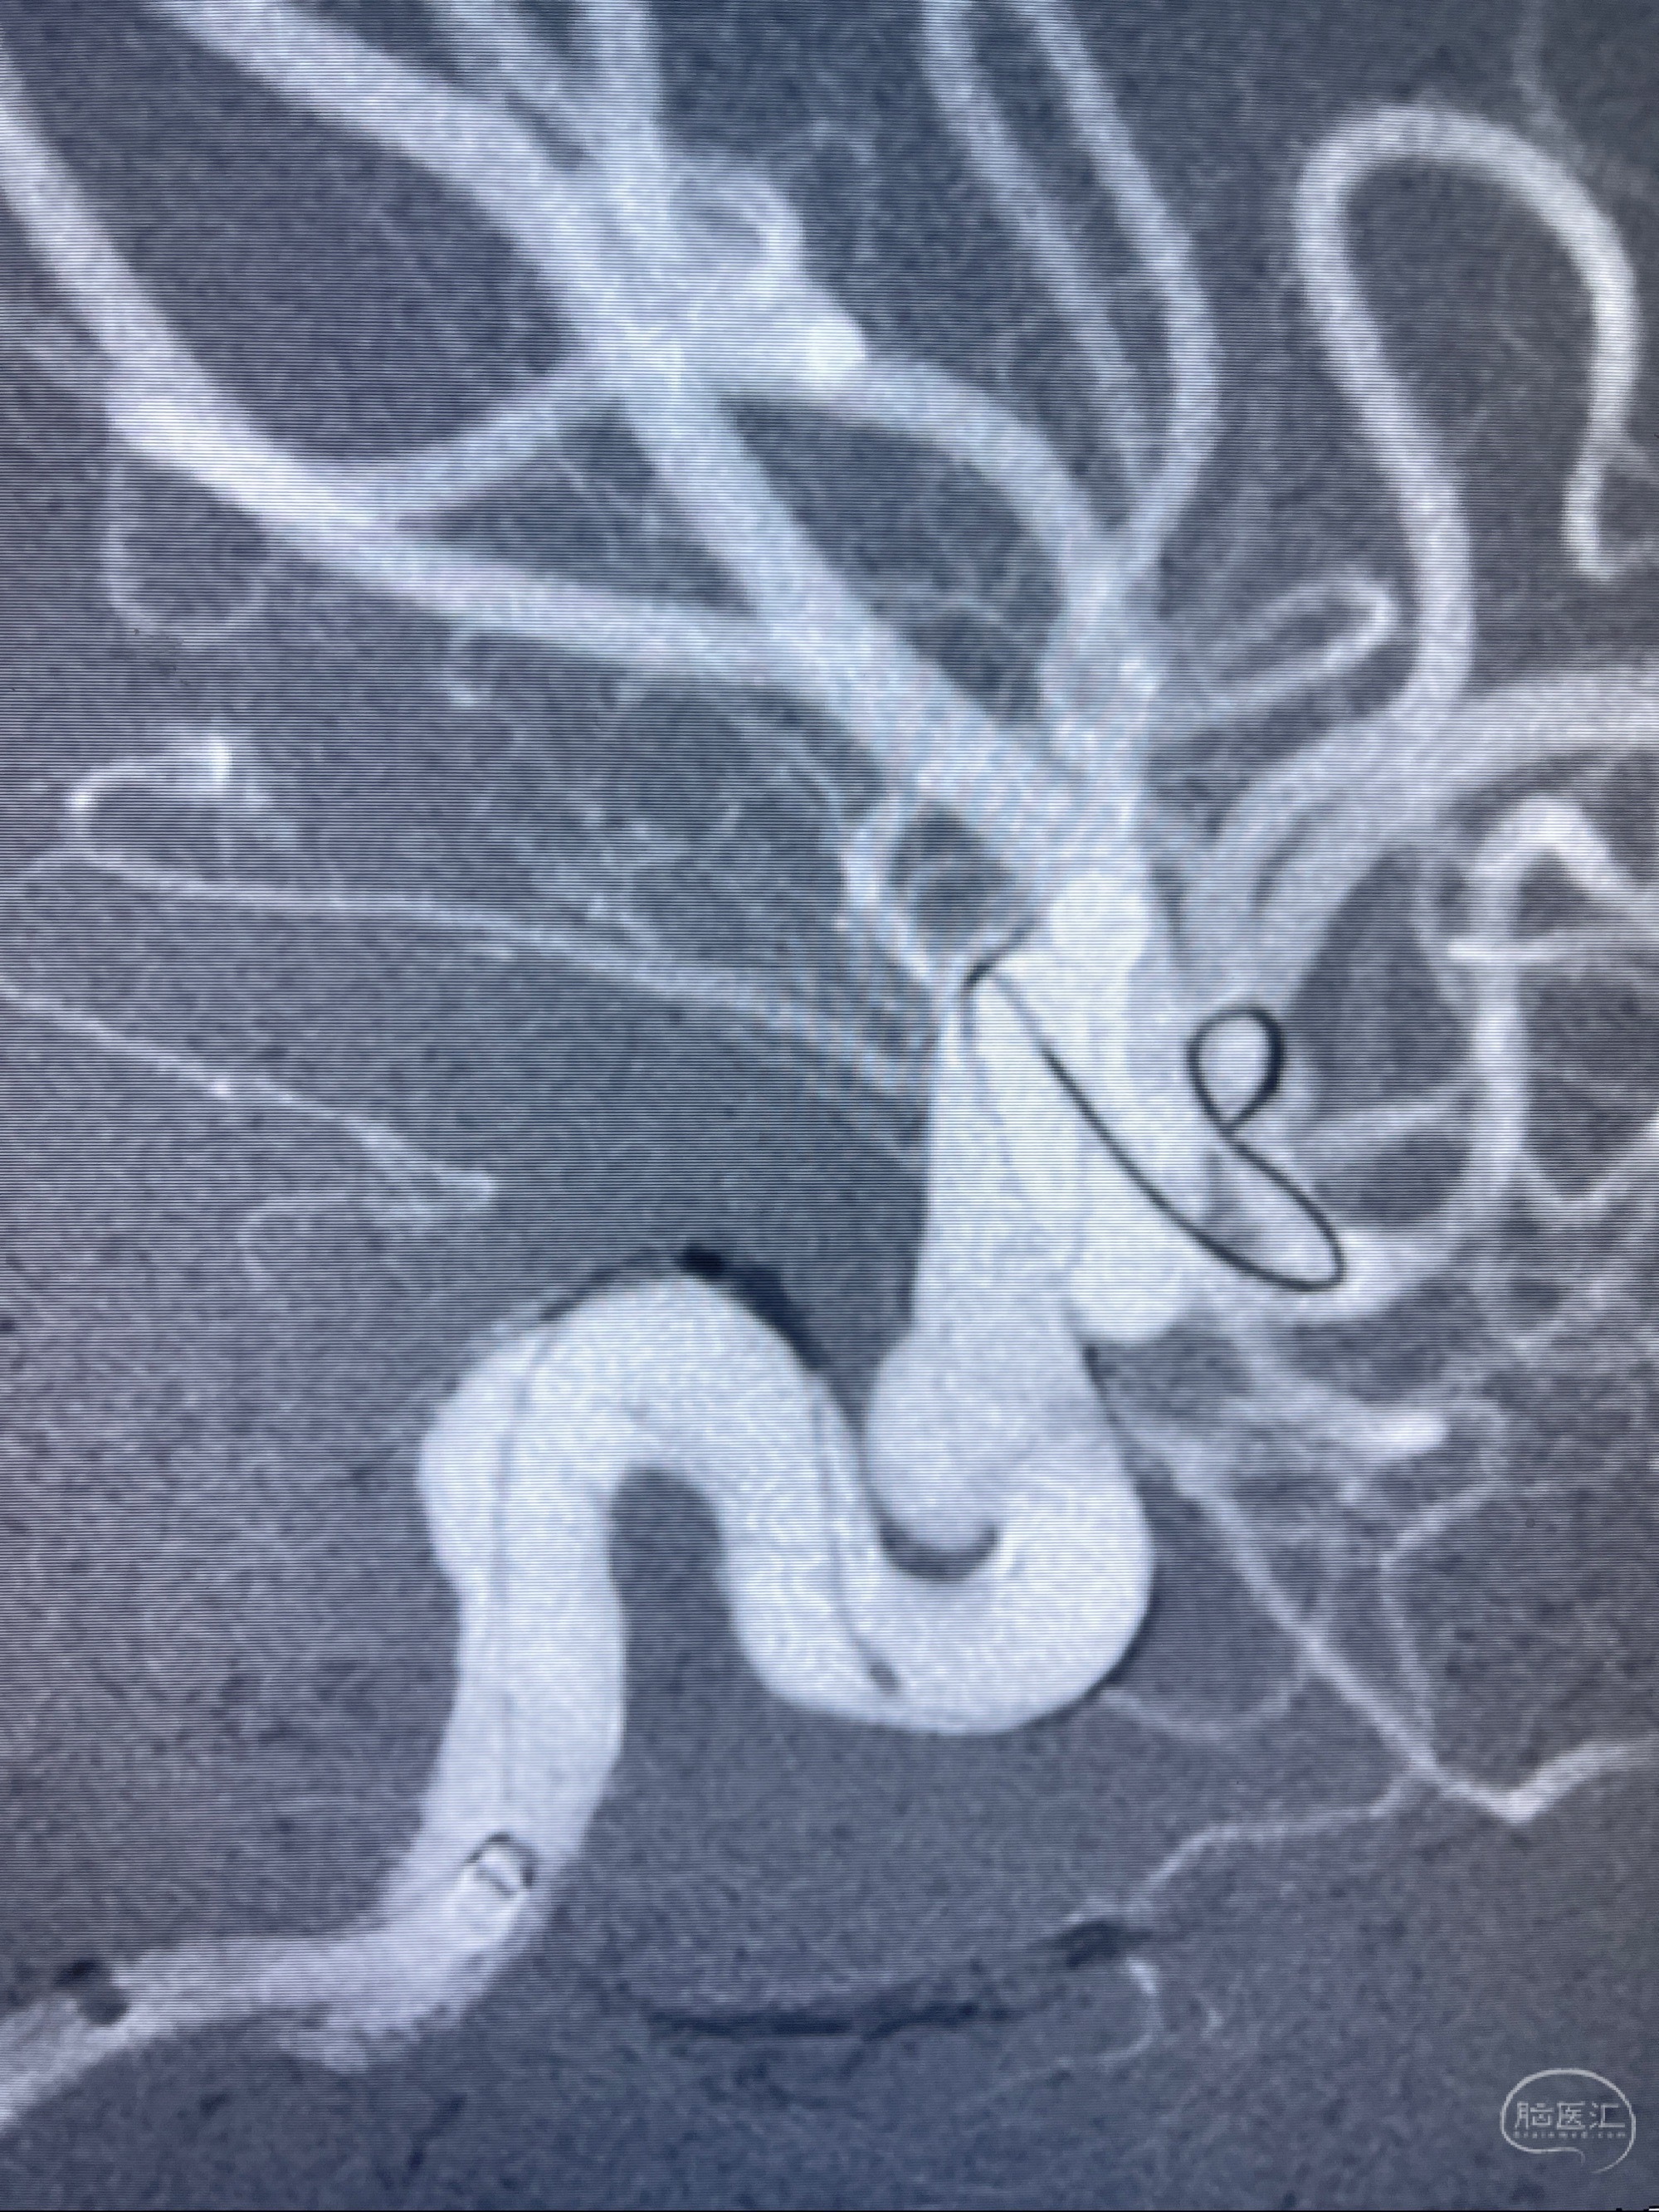

2023-07-27全脑血管造影:双侧颈内动脉眼动脉段动脉瘤,右侧较大

2023-08-01全麻下行双侧颈眼动脉瘤支架辅助栓塞

- pipeling4.5-20mm

- pipeline 4.0-20mm